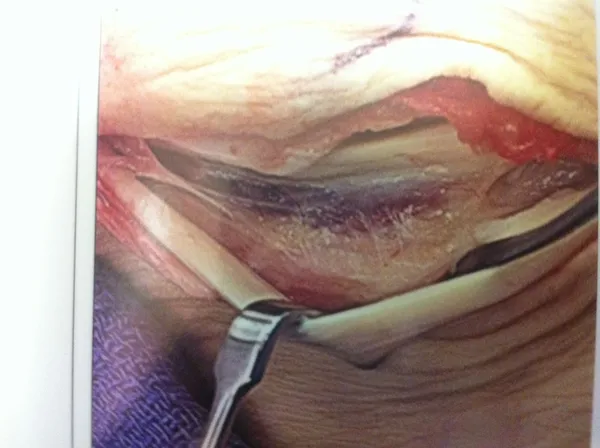

Pic of Split tear of the Peroneus Brevis and section that was removed. This is caused by the Peroneus longus constantly pushing the Brevis into the back of the fibula. It can be due to repeated microtrauma or one isolated traumatic event, i.e. ankle sprain or fracture).

Pic of Split tear of the Peroneus Brevis and section that was removed. This is caused by the Peroneus longus constantly pushing the Brevis into the back of the fibula. There was also a low lying muscle belly of the Brevis that was removed with the damaged tendon. This can be seen at the left side of the removed tendon. The tear can be due to repeated microtrauma or one isolated traumatic event, i.e. ankle sprain or fracture).